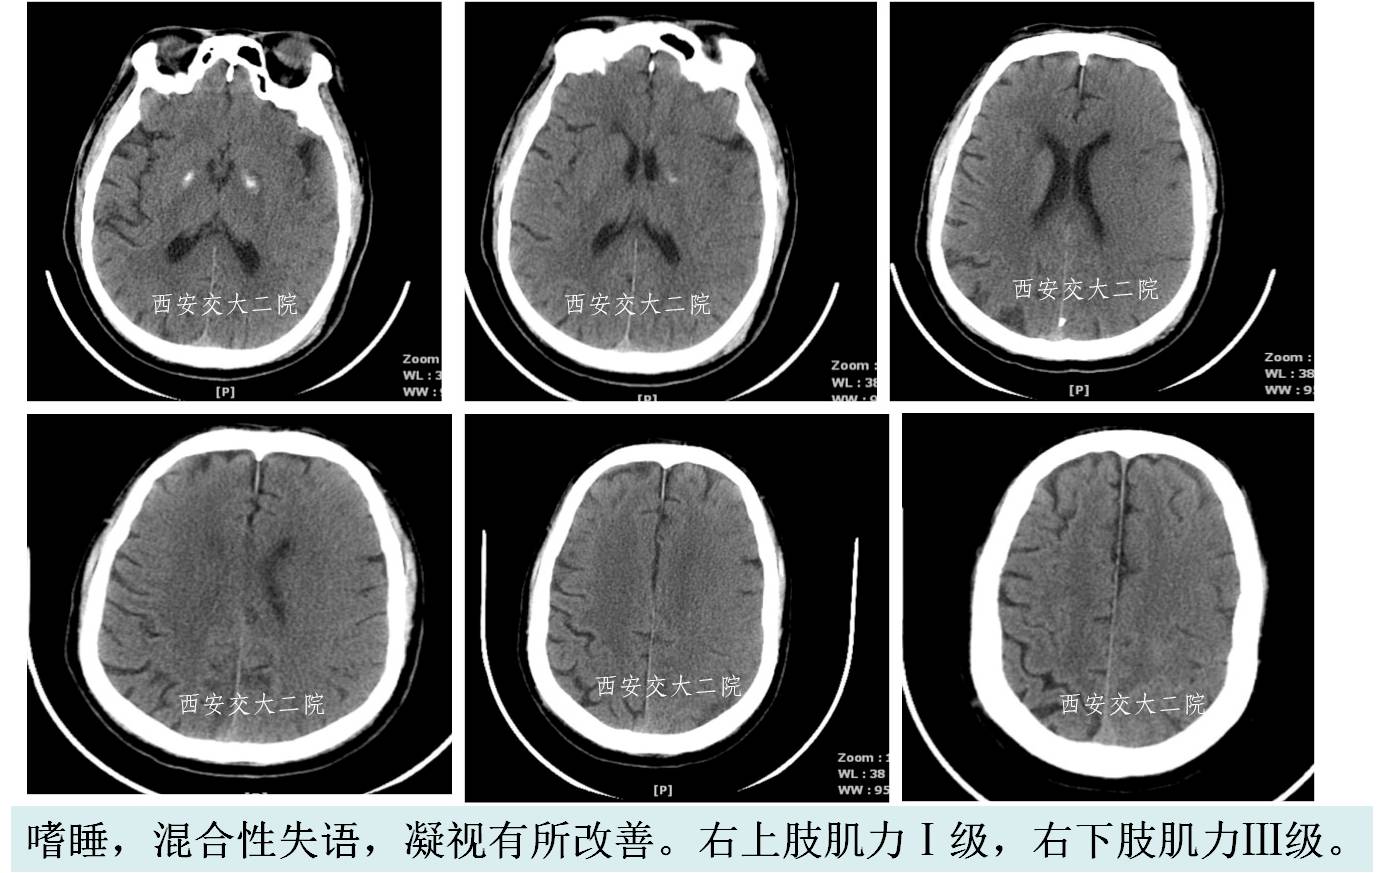

Case 1 颈内动脉C1段急性闭塞(2009年)

》男,70岁,突发右侧肢体无力3小时,DSA提示左侧颈内动脉起始段闭塞。

Case 2 左侧大脑中动脉溶栓+支架 (2009年)

》男,44岁,突发言语不能,右侧肢体活动不灵2小时。

》尿激酶10万后MCA未通,给予Apollo支架植入。

术后即刻CT

术后5天脑CT